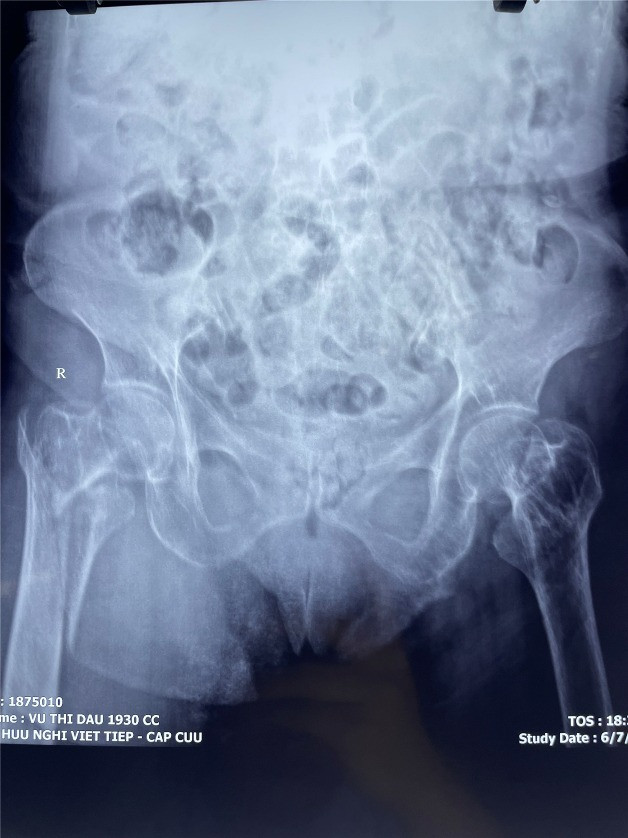

![]() |

| Gãy khối máu chuyển xương đùi của người bệnh trước phẫu thuật |